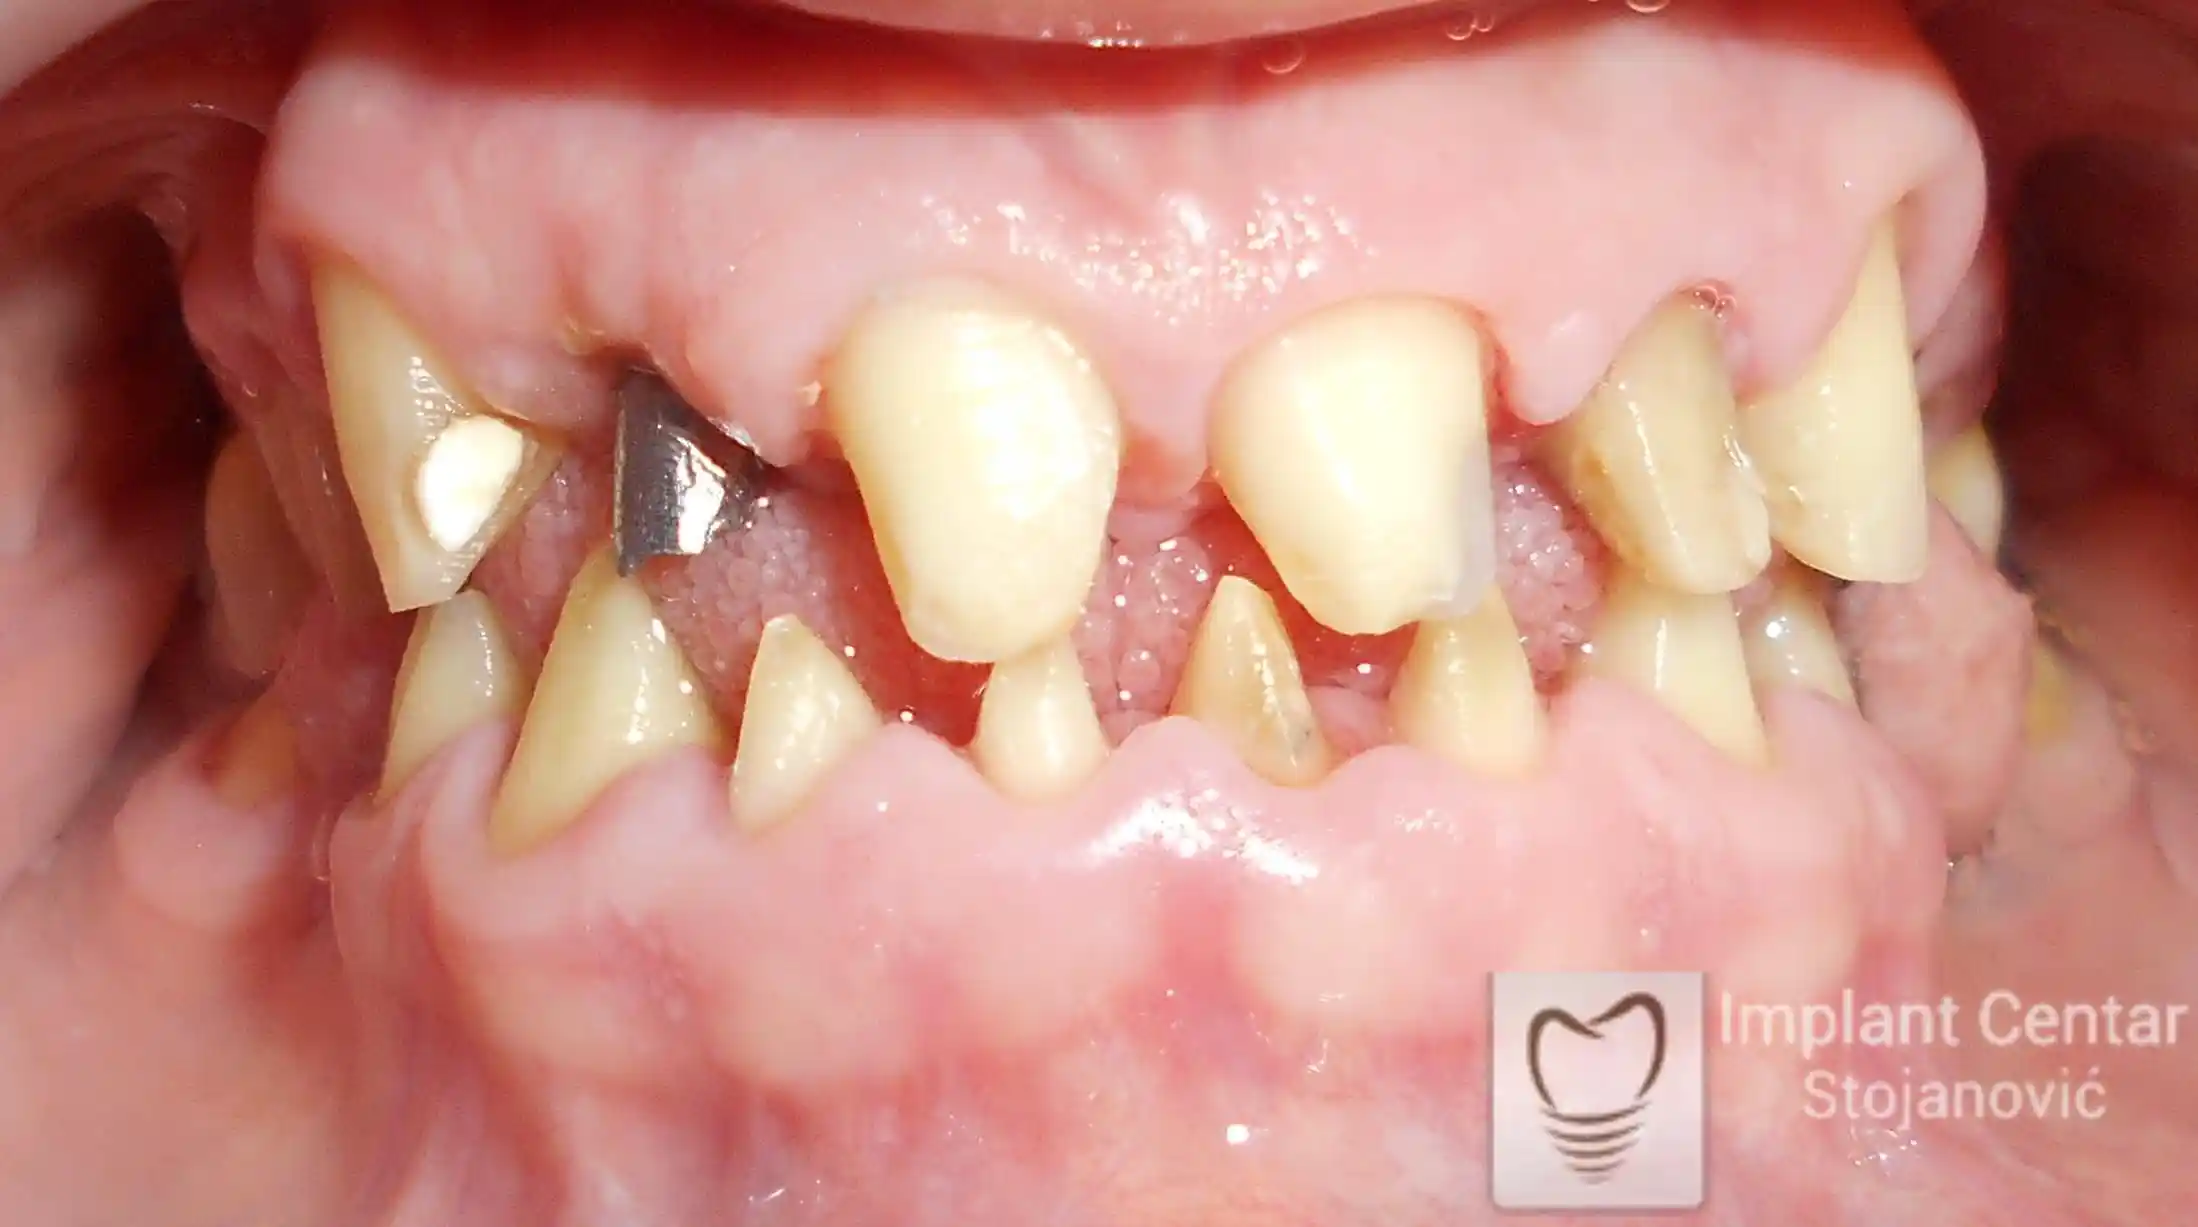

Na slikama 1, 2, 3 , 4  i  5 prikazan je izgled pacijenta pre početka terapije. Nakon detaljne kliničke i radiološke analize, doneta je odluka o vađenju zuba loše biološke vrednosti, dok su bezuba polja sanirana ugradnjom dentalnih implantata.

Kod pacijenta je došlo do značajne abrazije prednjih zuba, koja je nastala zbog gubitka zuba u  bočnim regijama gornje i donje vilice i nemogućnosti žvakanja u bočnim regijama. Pacijent je preopterećivao prednje zube prilikom žvakanja, što je vremenom dovelo do istrošenosti zubnih površina i pojave funkcionalnih problema.

Na slikama 1 i 2 prikazan je klinički izgled pacijenta pre početka terapije. Nakon detaljnog kliničkog pregleda, analize radioloških snimaka, kao i razgovora sa pacijentom o njegovim željama i očekivanjima, izrađen je sveobuhvatan plan terapije. Terapija je podrazumevala vađenje preostalih zuba, ugradnju dentalnih implantata i izradu fiksnog protetskog rada na implantatima.